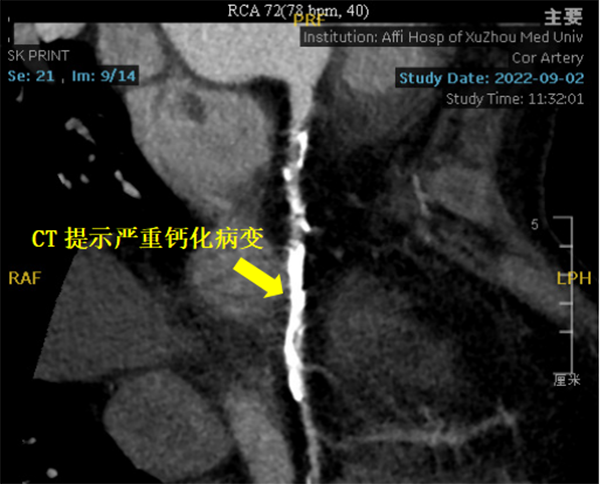

患者冠脈造影提示右冠狀動脈重度鈣化病變,狹窄程度達到90%-95%,左主干及左前降支彌漫鈣化伴中重度狹窄。潘德鋒主任團隊與心臟大血管外科王國祥主任團隊會診討論后,與患者家屬充分溝通病情,考慮到患者急性心梗、腦病等因素,決定采用冠脈支架植入術(shù)治療罪犯病變-右冠狀動脈重度鈣化病變。

2023年2月16日,在副院長楊煜的統(tǒng)籌指導下,心內(nèi)科冠脈專業(yè)專家組夏勇主任、徐通達主任、錢文浩主任、徐晤主任、陸遠主任等針對病例進行了充分的討論及術(shù)前準備,由潘德鋒主任進行手術(shù)操作。術(shù)中首先利用血管內(nèi)超聲明確患者冠狀動脈的鈣化情況及血管直徑,在血管內(nèi)超聲的指導下,選擇了4.0mm×12mm的沖擊波球囊,順利送入沖擊波球囊至鈣化病變部位,釋放脈沖,每次釋放10個脈沖,最終通過釋放80個脈沖,將鈣化斑塊進行了充分預處理,成功為患者植入了一枚冠脈支架,術(shù)后血管內(nèi)超聲顯示支架貼壁良好,患者癥狀明顯緩解,2月18日康復出院。